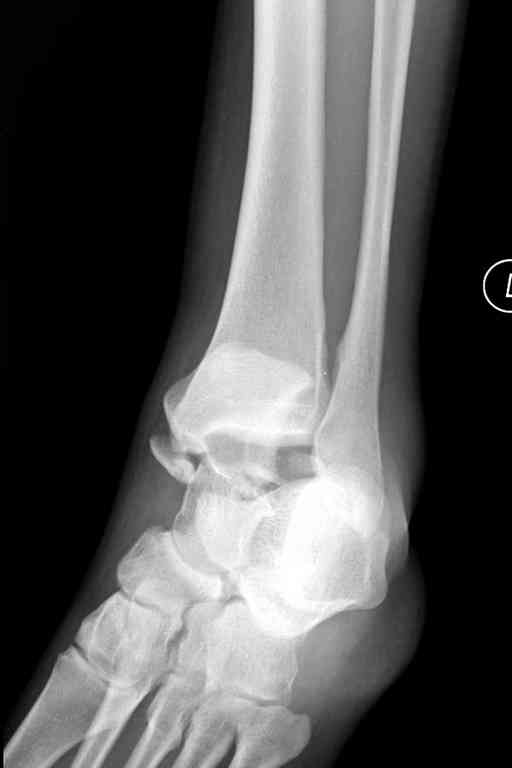

Здесь на фото примеры:

Переломовывих тарана с повреждением медиальной стороны. Через 4 часа после поступления проведена репозиция и фиксация тарана после Irrigation&Debridment. Частичное несращение медиальной лодыжки не беспокоит, вернулся к активному образу жизни. Полная нагрузка разрешена через 11 недель. Финальные снимки через 11 месяцев.

Второй случай прооперирован вчера.

10 дней назад поступил с открытым повреждением медиальной лодыжки и переломо вывихом таранной кости. Ургентно сделана репозиция с наложением наружного фиксатора + Irrigation&Debridment.

Во время репозиции выявили повреждение заднего сухожилия м. тибиалис и задней большеберцовой артерии. Медиальную рану удалось закрыть частично и установлен вакуум.

Дважды провели Irrigation&Debridment с заменой вакуума.

Вчера провели фиксацию.

Из-за многооскольчатости дистальной части малоберцовой, где невозможно было провести фиксацию шурупами, перелом зафиксирован подпирающей пластиной, которая должна служить дополнением отсутствующей дистальной части малоберцовой (lateral cortex substitute).

Для стабильности два шурупа на синдесмоз.

Медиальную рану с приближенными краями продолжаем вакуумировать (KCI). Наружный фиксатор оставлен на пару недель, надеюсь, небольшая рана будет гранулировать и закроется без кожной пластики. Фиксация медиальной ложыжки не планируется.